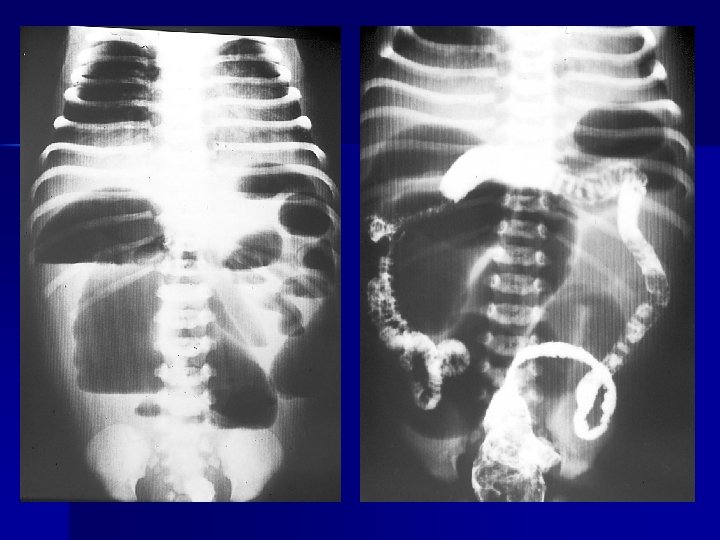

Radiologia Convenzionale (RC) • Transito gastrointestinale Contrastografia • Clisma opaco • Clisma mdc idrosolubile

Invaginazione

Invaginazione ileo-cecale

Malrotazione